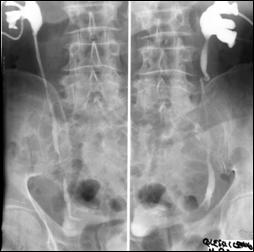

Diagnosticul diferential cu tuberculoza urogenitala

Vezica urinara are contururi greu delimitabile pe cistografie si pacientul are ureterohidronefroza bilaterala.

|

Figura 59. Vezica urinara "crispata", cu ureterohidronefroza bilaterala. |